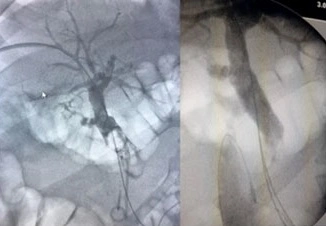

II trattamento richiede il posizionamento preliminare di un catetere ureterale, dotato di un palloncino in grado di occludere la via escretrice, a livello del giunto pieloureterale.

Viene creato un tramite nefrostomico percutaneo attraverso cui si introduce il nefroscopio. Quest’ultimo consente la visualizzazione diretta del calcolo e l’introduzione nella via escretrice di particolari sonde (ultrasuoni, laser). Queste consentono la frantumazione del calcolo renale.